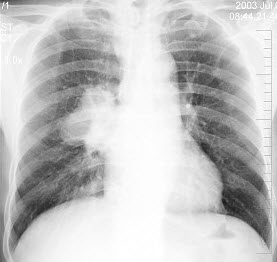

83、单项选择题

男,19岁,咳嗽、发热1周余,X线检查如图,最可能的诊断是()

A.左下肺不张

B.左侧胸膜肥厚

C.左下肺炎症

D.左侧胸腔积液

E.左下肺结核